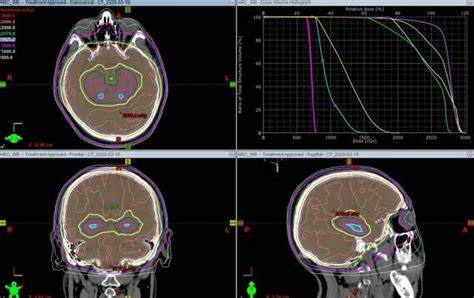

近年來,放療技術有了突飛猛進的發(fā)展,它能按照腫瘤體積形狀“雕刻”出包繞腫瘤的最佳等劑量線,同時隔離開需要保護的正常組織,達到了治愈疾病、保留患者的器官和節(jié)省費用的效果。

但21世紀進入了現(xiàn)代放療時代,是立體定位技術、影像技術、計算機技術、放療設備及技術等一系列新技術的結合體,放療已經(jīng)能夠做到正確、精確、足量地打擊目標,對部分早期腫瘤,可達到與手術切除同樣的效果,甚至比手術效果更好、創(chuàng)傷更小。